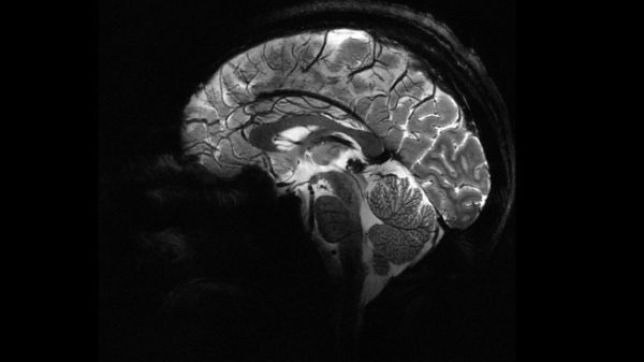

Pesquisadores do Comissariado de Energia Atômica da França (CEA) apresentaram na terça-feira (2/4) as primeiras imagens feitas pelo Iseult, o scanner de ressonância magnética mais potente do mundo. O aparelho tem capacidade de realizar imagens do cérebro com uma precisão inédita, o que pode ser fundamental para a detecção e tratamento de doenças neurológicas.

Com cinco metros de largura por cinco de diâmetro, quase o dobro da dimensão dos aparelhos em operação atualmente, seu campo magnético é inédito: conta com uma potência de 11,7 teslas. A título de comparação, os scanners em funcionamento hoje contam com no máximo 3 teslas.

Segundo o diretor de pesquisas do CEA, Nicolas Boulant, graças a esse imenso campo magnético é possível realizar imagens de uma precisão jamais vista do cérebro humano em apenas quatro minutos. No mapeamento feito pelo Iseult, até mesmo as veias do córtex podem ser observadas.O jornal Le Figaro destaca que o projeto é fruto de uma parceria entre a França e a Alemanha. No total, foram 25 anos de trabalhos conjuntos da ciência e indústria, com um investimento de € 70 milhões.

Com a descoberta, os pesquisadores esperam agora detectar as atrofias do hipocampo que caracterizam a doença de Alzheimer, por exemplo. Além disso, o Iseult também tem a capacidade de visualizar os neurônios em tempo real, o que pode ajudar a esclarecer várias condições psiquiátricas e doenças neurodegenerativas.